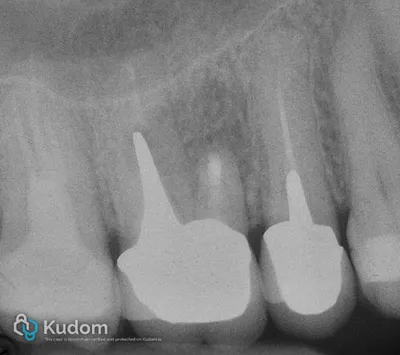

Intervento di microchirurgia apicale della radice mesio-vestibolare di un molare superiore con lesione periapicale estesa, secondaria alla mancata individuazione del canale MB2.